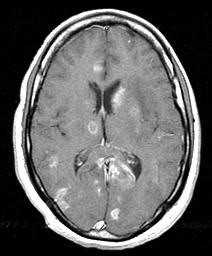

Инфекции быстро прогрессируют, особенно токсоплазмоз. При МРТ виден выраженный отек вокруг очага. Контрастируется при МРТ токсоплазмоз обычно по кольцевому типу.

МРТ головного мозга. Т2-взвешенная аксиальная МРТ. Токсоплазмоз.

Лимфома также контрастируется на МРТ по кольцевому типу, но гипоинтенсивна на Т2-взвешенных МРТ головного мозга. По локализации лимфома чаще располагается перивентрикулярно, в то время как очаги токсоплазмоза в области базальных ганглиев и сопровождаются значительным отеком.